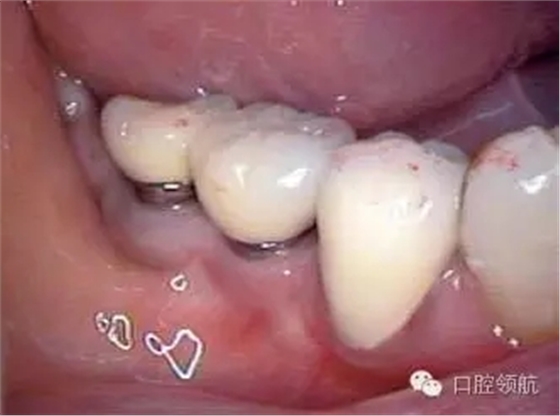

患者, 5 3 歲, 女, 2 0 0 2 年2 月(右下第6、7顆牙) 接受種植治療,采用了一次手術(shù)的方法,SwissPlus種植體(Zimmer公司,直徑3.7mm×長徑10.00mm),6個月后取印模,制作混合陶瓷上部修復體(圖1)。

圖1 上部修復體安裝后的口內(nèi)照片